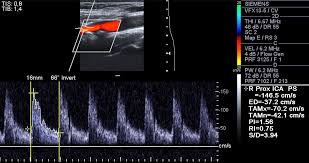

경동맥의 협착 정도와 혈류 속도를 확인해 향후 뇌졸중 발생 가능성을 예측할 수 있습니다.

혈관 내막 두께, 협착 정도, 혈류 속도 등을 확인할 수 있으며, 결과에 따라 추가 정밀검사가 필요할 수 있습니다.